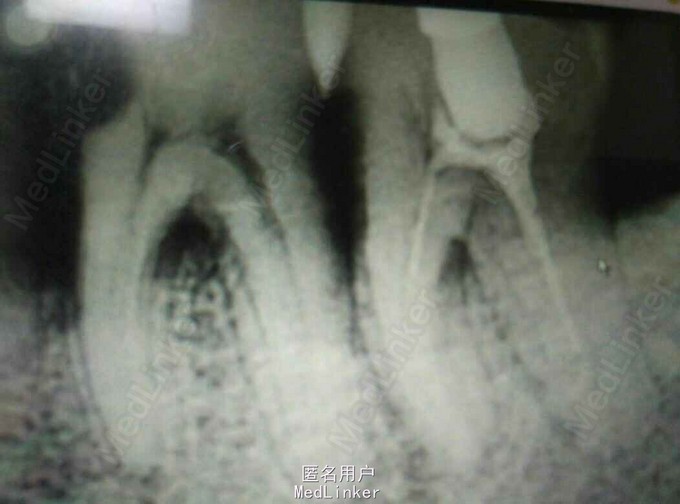

主诉:左下后牙疼痛两日余,加重一日。 现病史:左下后牙近来疼痛不适,一天前加重,影响其正常的饮食及休息,前来就诊。 既往史:高血压,糖尿病 检查:36近中邻面食物嵌塞,探诊( +),叩(+),冷(++),无松动,37牙合面大面积充填物,松动3度,探及颊侧近中远牙周袋深均>7MM,根分叉2度,叩(-), X线示:36近中邻面龋坏近至髓腔 37根管治疗不完善 诊断:36慢性牙髓炎急性发作 37中度牙周炎 建议:1 36根管治疗择期加钉冠修复 2 37根管再治疗后观察 处理:1 36去龋未净露髓,全身状况稳定,必麻下揭髓顶,降牙合,丁香油棉球引流; 37降牙合,去除原充填物,溶胶,反复冲洗,碘棉引流; 两日后复诊 常规医嘱